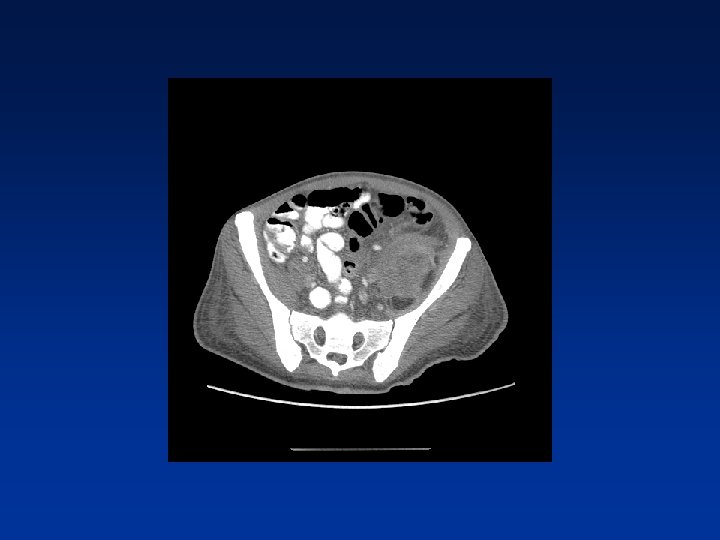

CASE